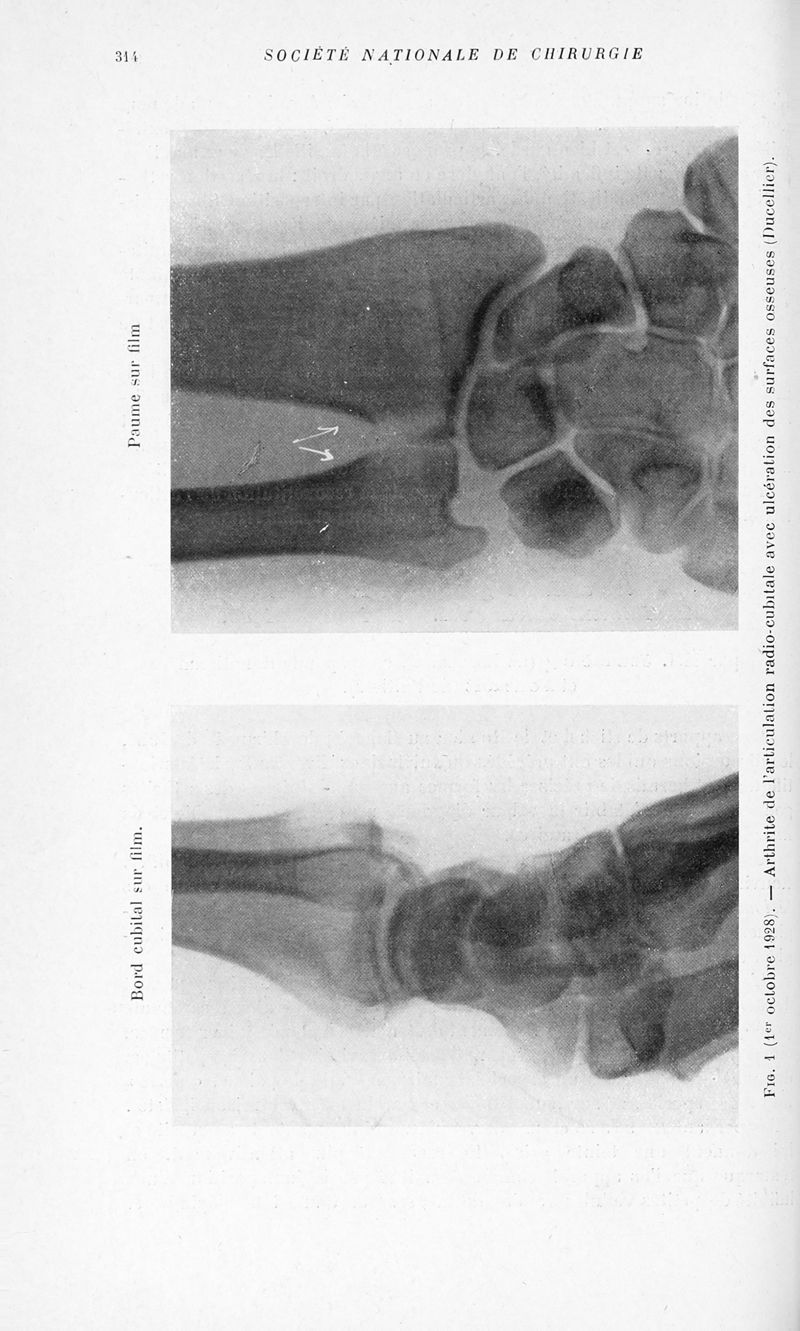

Bulletins et mémoires de la société nationale de chirurgie

Tome LV, 1929. - Paris : Masson, 1929.